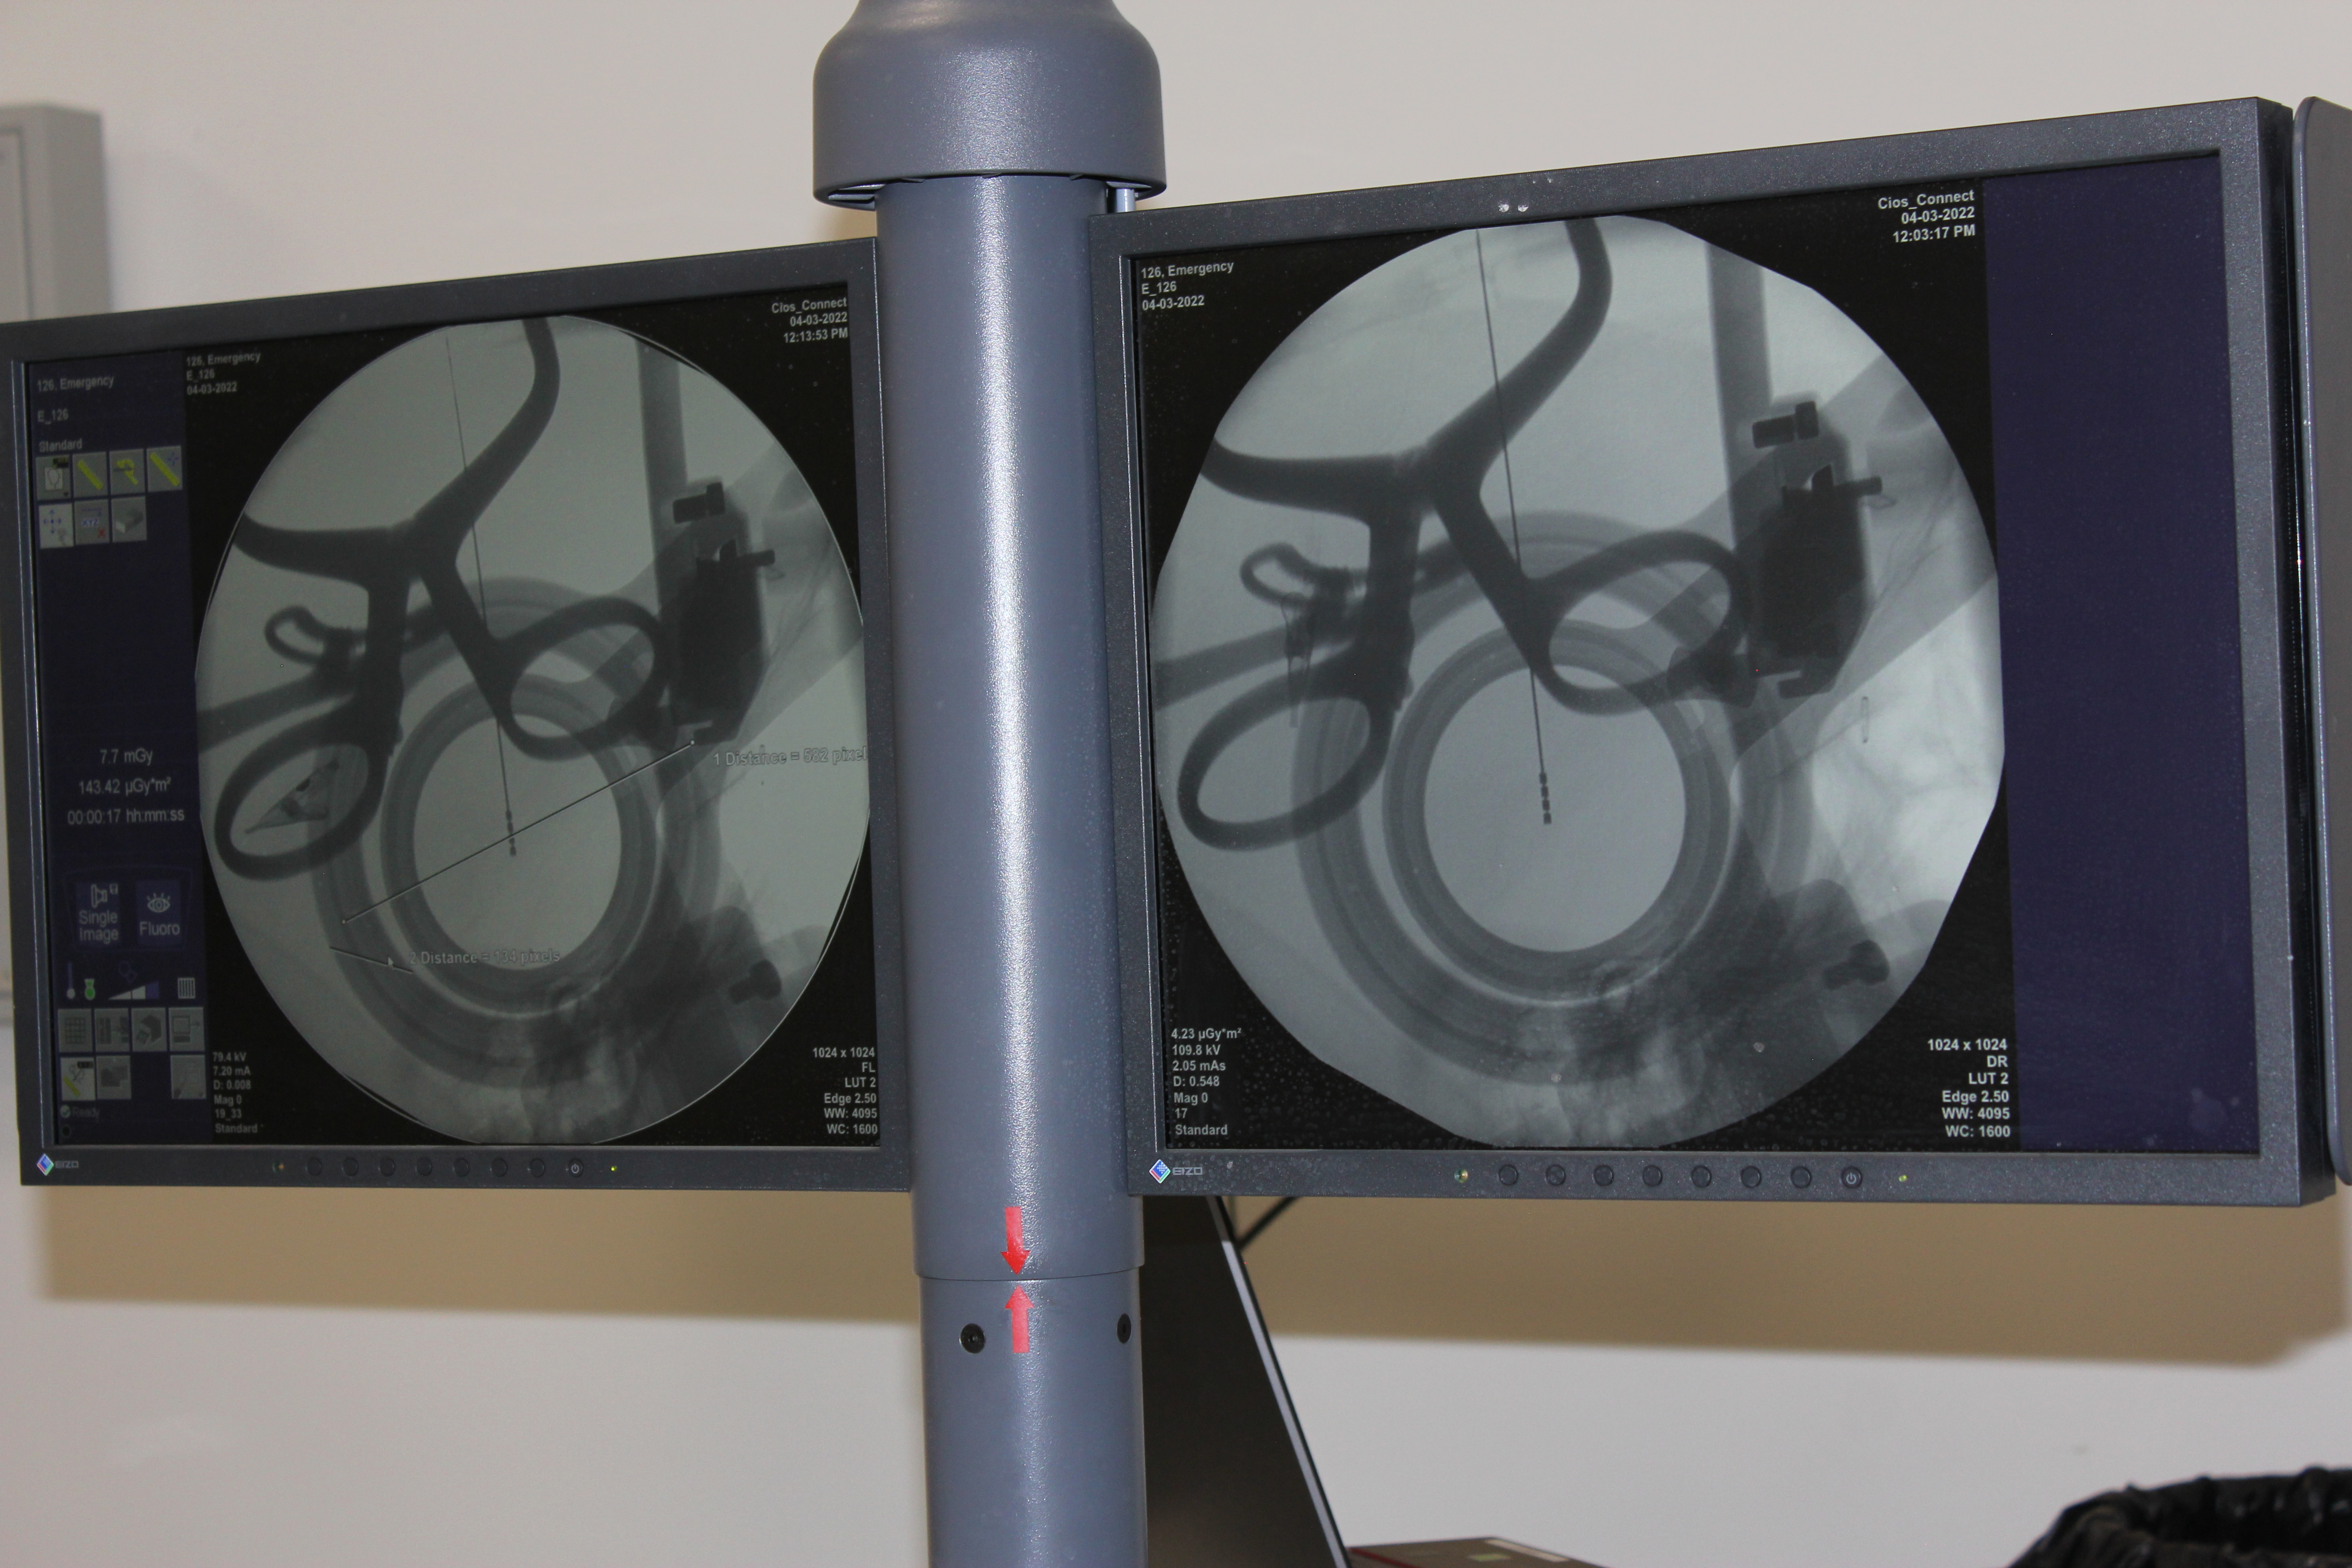

«Արաբկիր» ԲՀ-ԵԴԱԻ նյարդաբանության և էպիլեպտոլոգիայի, ինչպես նաև նյարդավիրաբուժության ծառայությունները հագեցած են մասնագիտական գործիքային հետազոտությունների համար անհրաժեշտ ժամանակակից սարքավորումներով: Այստեղ կատարվում են երկարատև և կարճատև վիդեո ԷԷԳ` էլեկտրաէնցեֆալոգրամմա կամ էլելտրաուղեղագրություն, նեյրոսոնոգրաֆիա, գլխի համակարգչային տոմոգրաֆիա, ստերեոէլեկտրաուղեղագրություն և այլն: Դրանք թույլ են տալիս կատարել հնարավորինս ճշգրիտ ախտորոշում և ապա ընտրել բուժական ճիշտ տակտիկա` ի շահ պացիենտների: